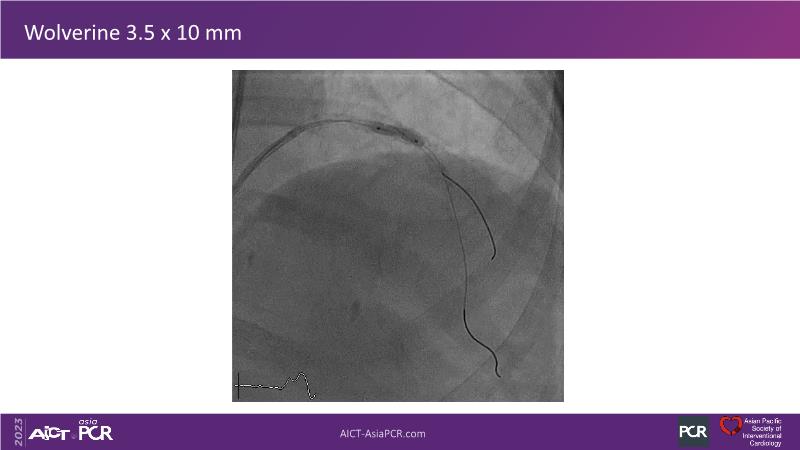

• To see advantages of RotaCUT as part of lesion preparation in left main bifurcation